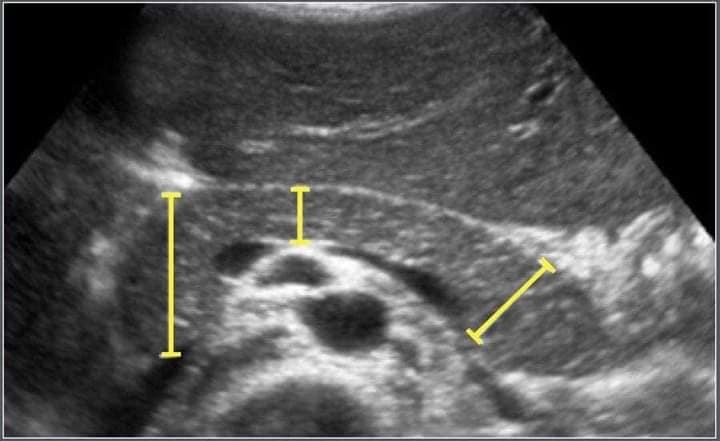

Эхний зураг: 3 настай охины #НОЙР_БУЛЧИРХАЙН_АРХАГ_ҮРЭВСЭЛ болсон байгаа нь/доод зурагтай харьцуулна/

Хоёр дахь зураг: Хэвийн үед нойр булчирхай ингэж харагдана